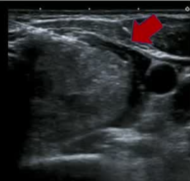

单色和彩色SMI成像血管化,插入穿刺针到动脉中心。

流微血管成像(SMI Superb microvascular imaging)【Machado P 2016】 - 微血管血流成像 - 先进的杂波抑制提取血流信号 - 从大血管到小血管 经峡部入路【Shin JH 2012 Vorlander C 2018】

当可以识别出明显的供血动脉时,动脉优先消融技术可用于血管充血的结节。在最近的研究中,用CD(color 多普勒)和PD(power 多普勒)检测供血动脉。与其他多普勒技术相比,使用SMI更详细地评估结节微血管结构。动脉优先技术用于减少甲状腺结节RFA中产生的热量的分散,但在随访中也增加了该手术的疗效【Park HS 2017】。